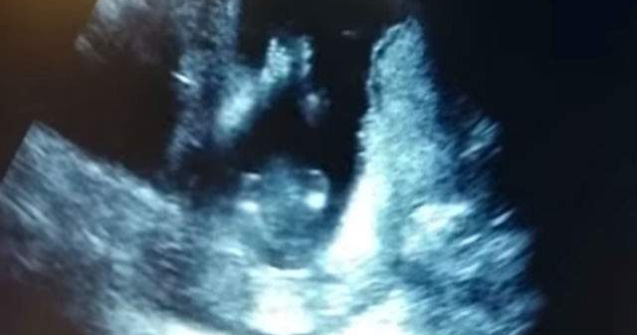

Cat de frumos! Un clip postat recent pe YouTube arata cum un bebelus bate din palme in pantece, in timp ce mama sa ii canta.